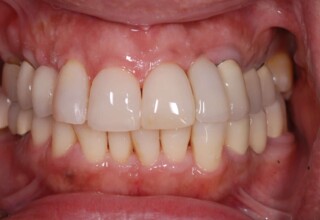

Extensive case with crowns in almost all teeth

Extensive case with crowns in almost all teeth due to extensive wear, old restorations, posterior root canals and aesthetic concerns. Patient (60years old) presented with intense bruxism which he never had treated. Consequently, he obtained very deep cervical abrasions which jeopardized tooth integrity. Restorations (fillings) were executed mainly with adhesive resinous materials and three custom cast post and cores. Temporary crowns were placed to evaluate the desired size, shape and position of the teeth before permanent crown fabrication.

Initial smile

Final Smile